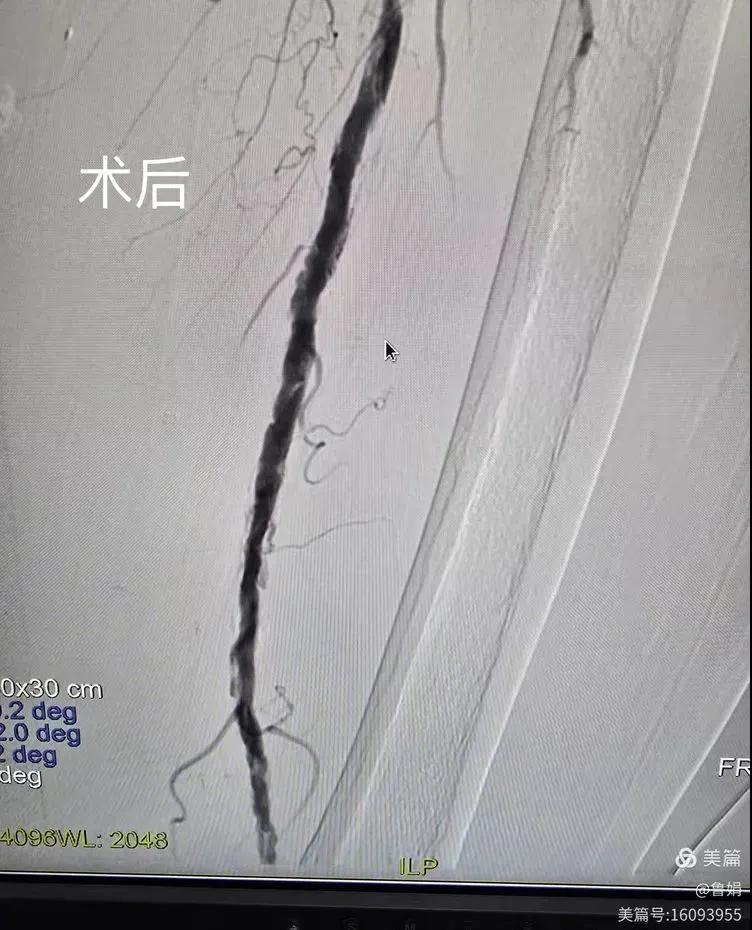

據(jù)悉,該患者,女,73歲,下肢動脈硬化閉塞癥,“以靜息痛,間歇性跛行”入院,CTA評估:股淺動脈,腘動脈間斷性多段重度狹窄,外二科血管外科團隊根據(jù)患者病情,結(jié)合檢查結(jié)果,經(jīng)過科室會診后,決定對該病人行介入治療。手術由周創(chuàng)業(yè)副主任與北大一院血管外科專家郭宏杰教授聯(lián)合開展,對股淺動脈,腘動脈重度閉塞段行血管開通+藥涂球囊擴張成形,術后狹窄明顯緩解,血流恢復!